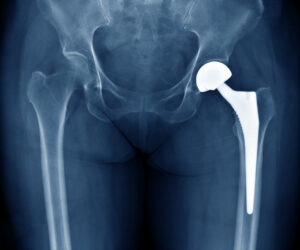

Kalça eklemi hasar gördüğünde yerine takılan yapay bir eklemdir. Genellikle ileri derecede osteoartrit, kırık veya diğer hastalıklar sonucu uygulanır. Kalça protezi, metal, seramik ve plastik malzemelerden yapılır. Ameliyat sonrası hastalar ağrısız bir yaşam sürmeyi hedefler. Protez, hareket kabiliyetini artırarak hastanın yaşam kalitesini iyileştirir.

Kalça protezi ameliyatı genellikle genel anestezi veya spinal anestezi altında yapılır. Ameliyat öncesinde hastanın durumu değerlendirilir ve gerekli testler yapılır. Cerrah, kalça eklemine erişmek için kasları ve dokuları geçici olarak ayıracak bir kesi yapar. Bu kesi genellikle uyluk bölgesinin yan kısmında yer alır. Eski ve hasarlı kalça eklemi, genellikle femur başı (uyluk kemiği) ve asetabulum (kalça çukuru) çıkarılır. Bu bölgelere protez yerleştirilecektir. Protezin her iki ana parçası yerleştirilir. Asetabuluma metal veya seramik bir kaplama yerleştirilirken, uyluk kemiğine uygun bir metal başlık takılır. Bu parçalar birbirine uyumlu şekilde tasarlanmıştır.

Protez, kemikle birleşerek sağlam bir bağ oluşturur. Kemik iyileşmesi ve protezin düzgün çalışması için bu aşama büyük önem taşır. Protez yerleştirildikten sonra, kesi dikkatlice kapatılır ve dikişler atılır. Ameliyat sonrası hastalar genellikle bir süre hastanede kalır ve ağrı yönetimi uygulanır. Fiziksel terapi süreci, kalçanın fonksiyonel hareketliliğinin tekrar kazanılması için oldukça önemlidir. Kalça protezi ameliyatı genellikle başarılı sonuçlar verir ve hastaların yaşam kalitesini artırır. Ancak her cerrahi müdahalede olduğu gibi, komplikasyon riski de bulunabilir. Bu yüzden hastaların uygun bir değerlendirmeden geçmesi gereklidir.